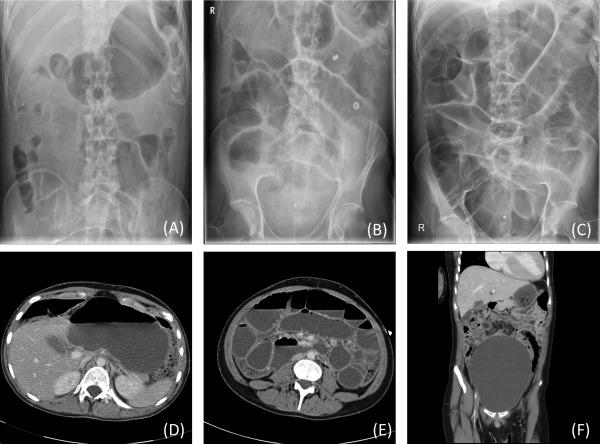

Acute refractory intestinal pseudo-obstruction in MELAS: efficacy of prucalopride.

Neurology. 2014 May 27;82(21):1932-4. doi: 10.1212/WNL.0000000000000458. Epub 2014 Apr 30.